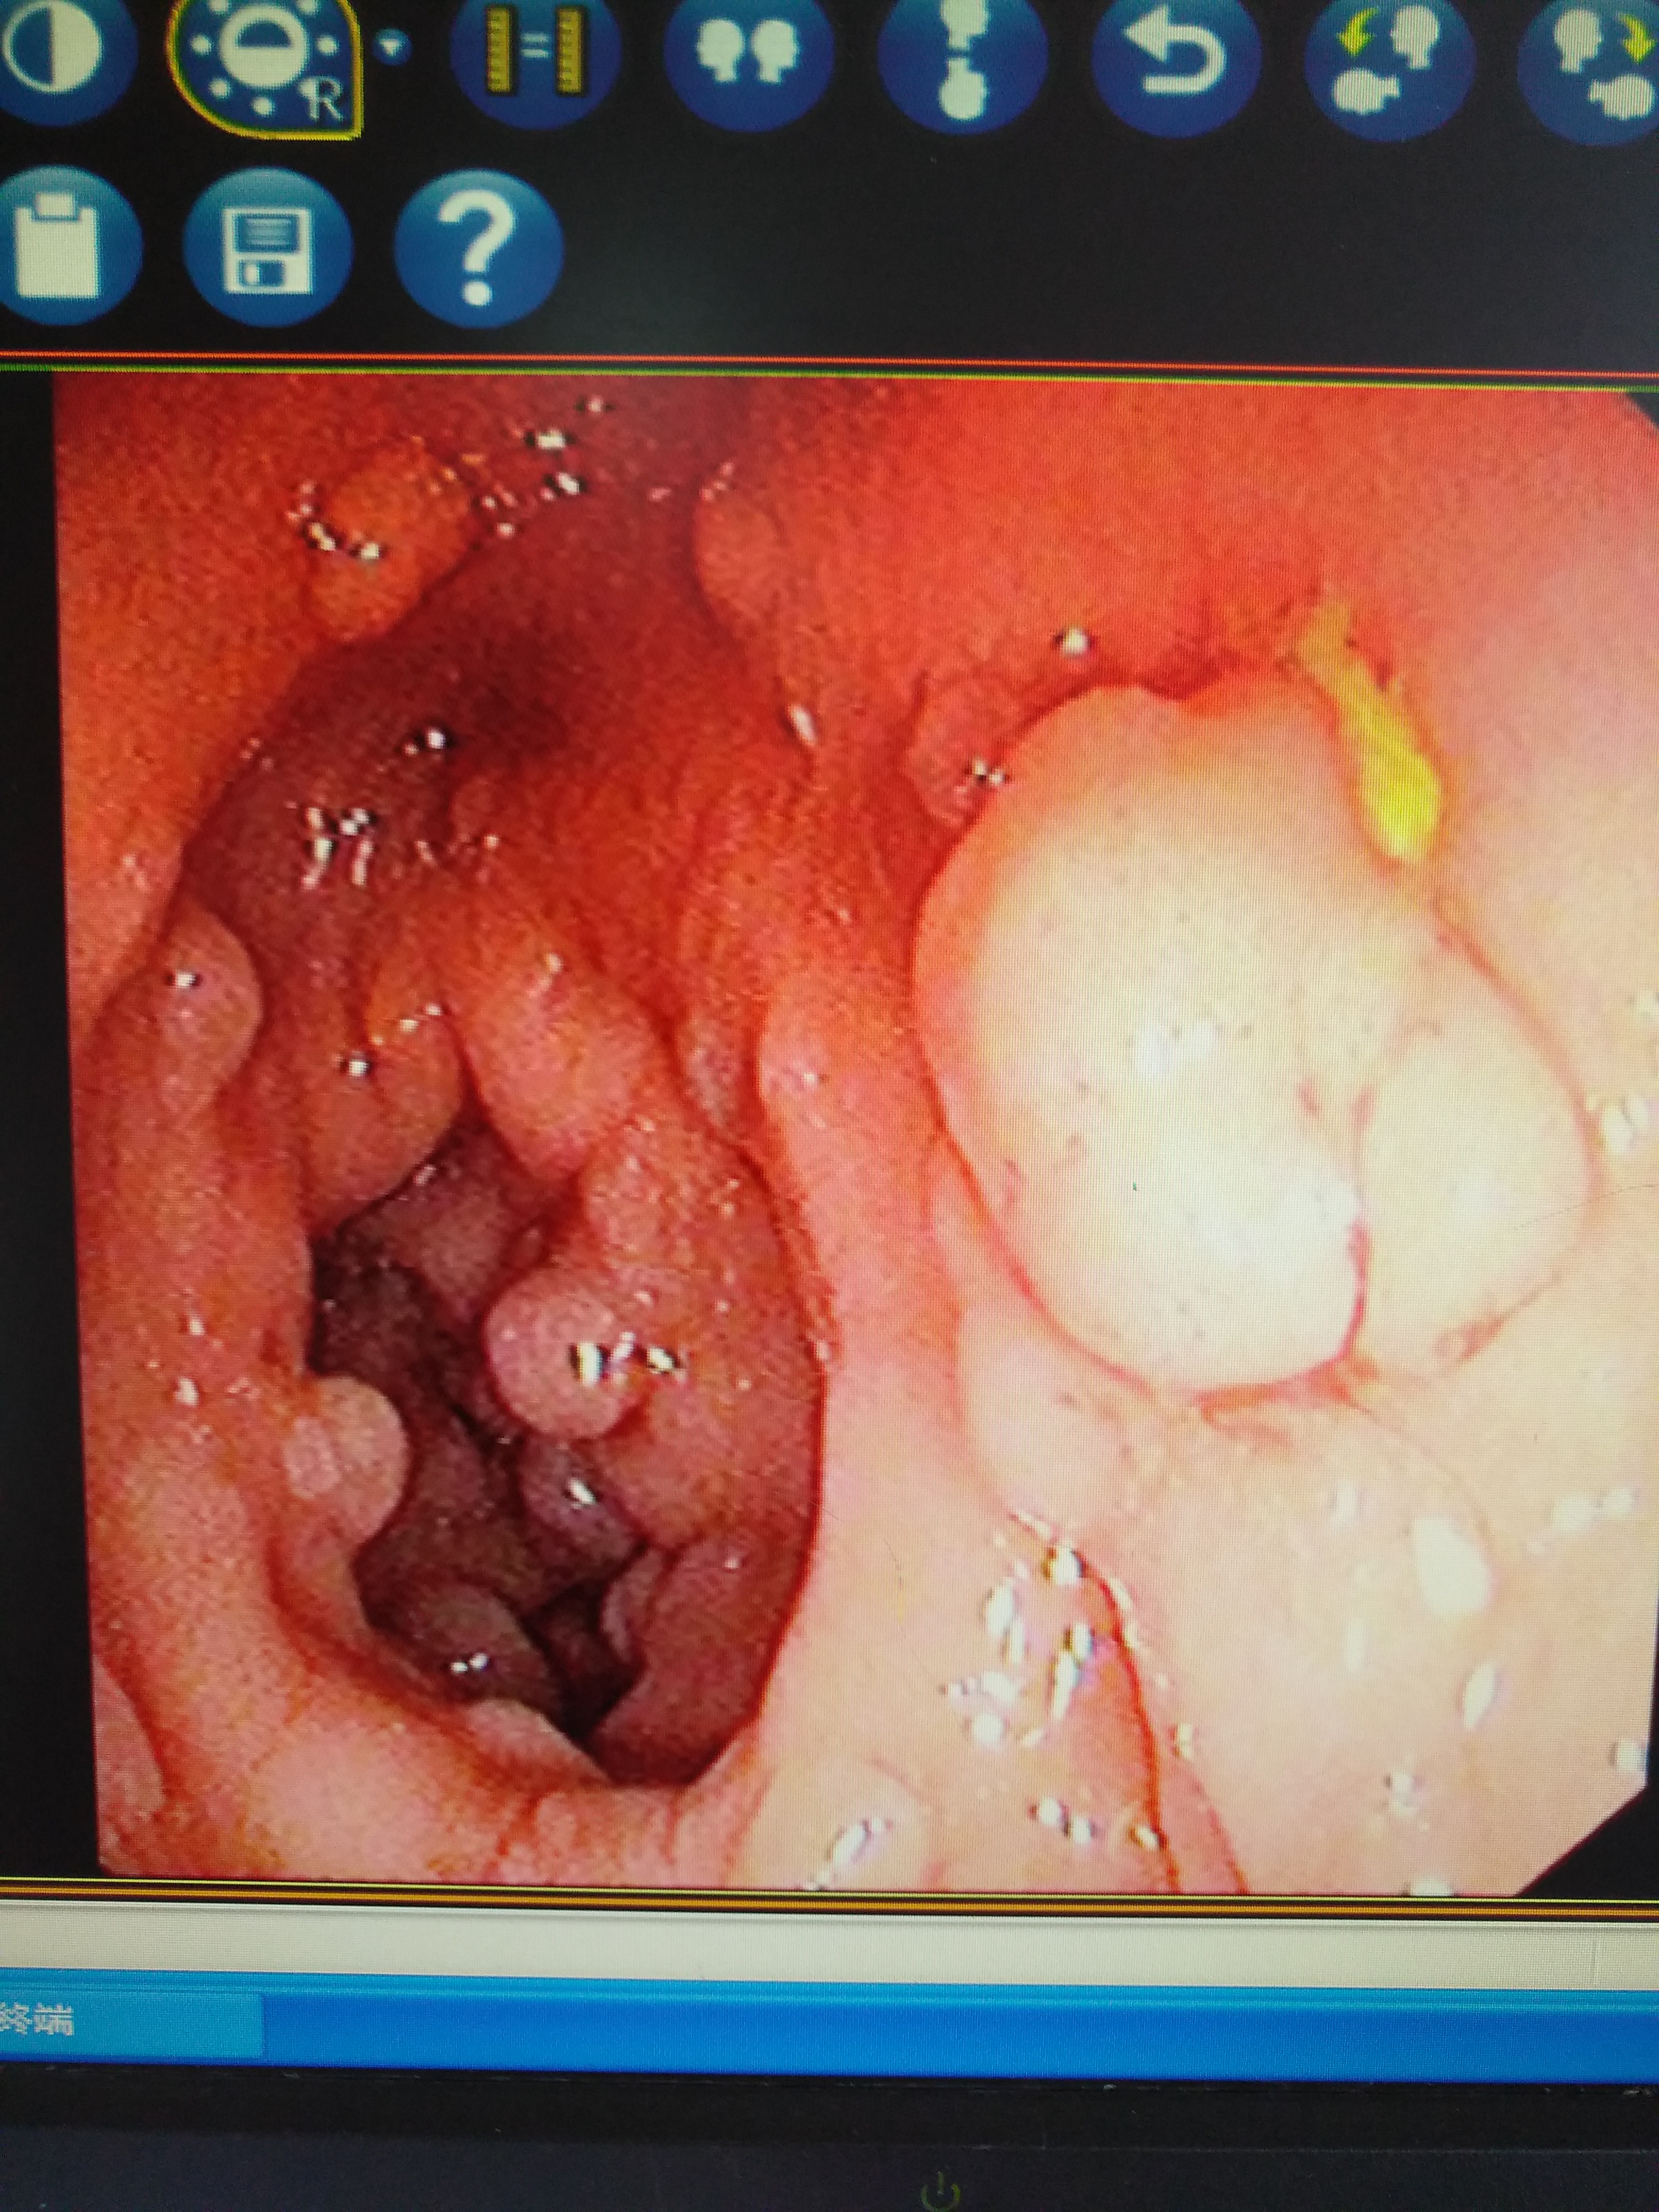

2、多发性胃肠息肉:息肉可发生于整个胃肠道,数目多少不等,息肉大多表面光滑,呈桑堪状或分叶状。带蒂或者无蒂,大多为炎性息肉,错构瘤。